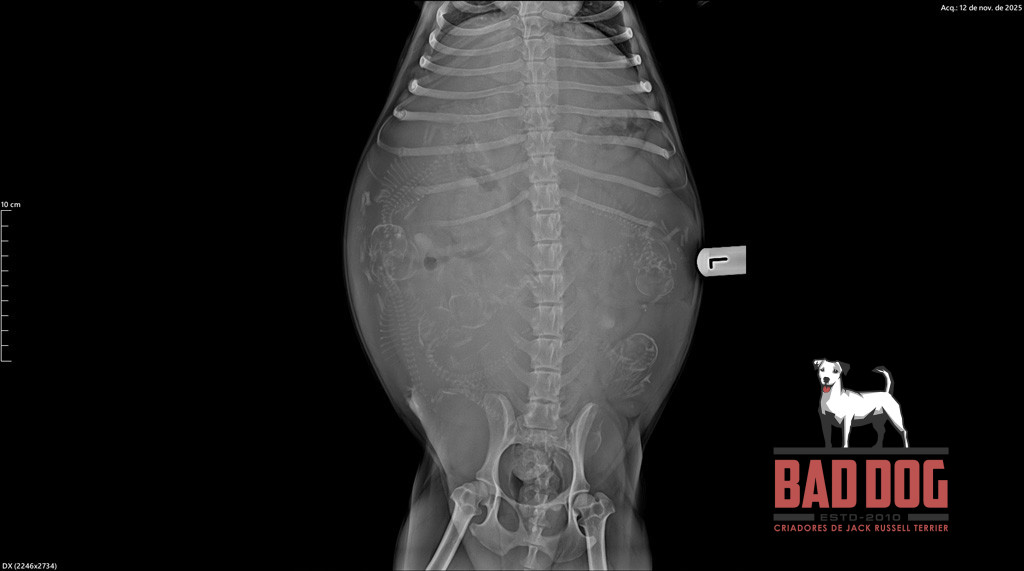

PHI2_oliva-rx phi2_litter_2

4 of 36